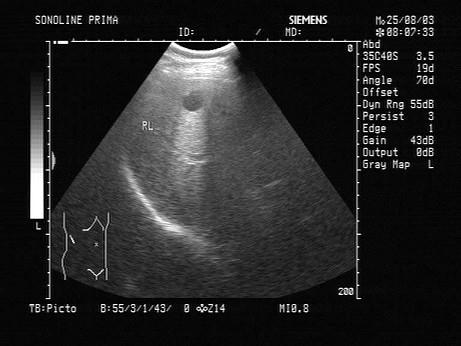

问题 女,50岁,上腹不适。结合超声声像图,诊断为?(?)

选项 A.肝血管瘤 B.肝癌 C.炎性假瘤 D.肝脓肿 E.肝囊肿

答案 E